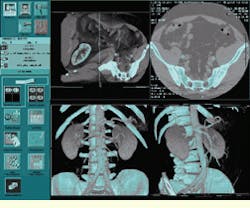

FIGURE 3. GE Medical Systems LightSpeed CT system provides radiologists with several views in addition to the original CT slices (top right), including volume renderings (bottom).